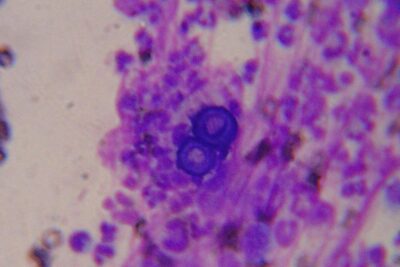

La forma micelial de B. dermatitidis es septada e hifal. Las hifas son aplanadas y ramificadas en ángulo recto. La colonia de hongos en Agar Sabouraud se ve rugosa y blanquecina. La forma levaduriforme tiene una estructura redondeada o elipsoidal y mide entre 8 y 15 micras de diámetro. Las células son gruesas y contienen una pared celular resistente y una cápsula. La coloración de la célula es parduzca y granulada, lo que le da un aspecto similar a una pelota de béisbol.

La forma levaduriforme de B. dermatitidis se multiplica por gemación, lo que significa que una célula madre produce una célula hija en su superficie. Las células hijas crecen hasta convertirse en células maduras y comienzan el proceso de gemación nuevamente. Las células hijas se liberan y forman una colonia de hongos en los tejidos afectados.